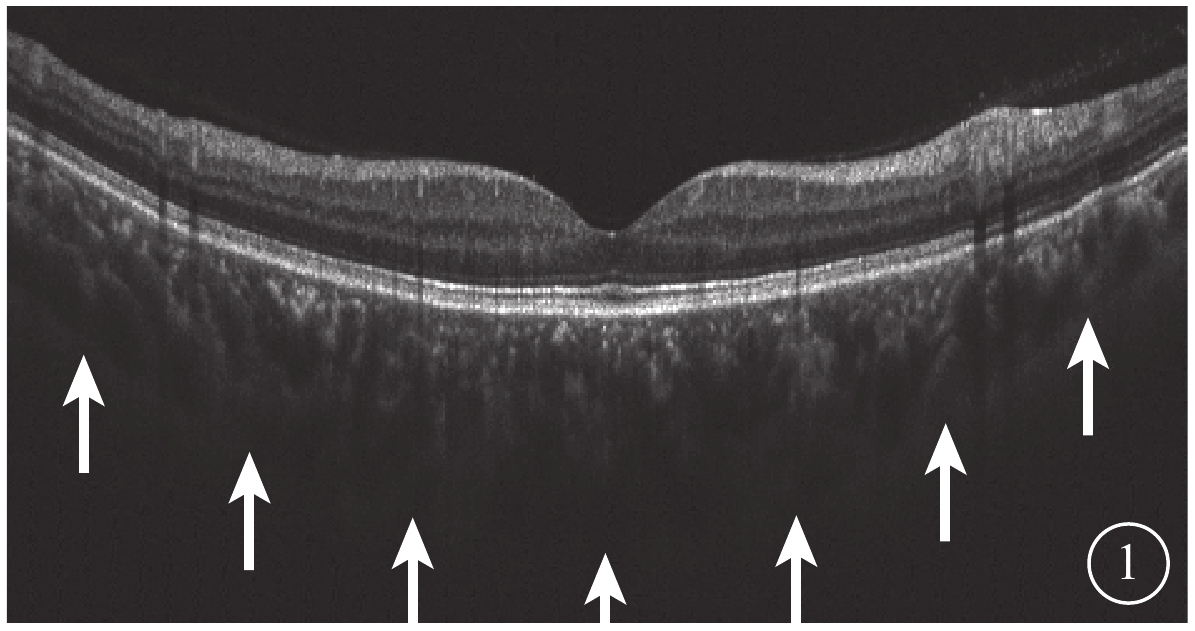

所有受檢者均于下午2:00~6:00行最佳矯正視力、屈光度、眼壓、裂隙燈顯微鏡、間接檢眼鏡、SS-OCT檢查和AL測量。采用德國Zeiss公司IOL-Master測量AL。采用日本Topcon公司Triton OCT儀以波長1050 nm,掃描速度100 000次/s對黃斑區進行掃描。黃斑區12.0 mm直徑行12條放射線SS-OCT掃描;黃斑區3.0 mm×3.0 mm行SS-OCTA掃描。由另一位未知研究對象分組的醫生選取圖像質量最高的一張SS-OCT圖像,測量黃斑中心凹下視網膜色素上皮層外界至鞏膜內界強反光線的垂直長度作為中心凹下脈絡膜厚度(SCT)(圖1)。截取Bruch膜下1/2脈絡膜厚度所在層面SS-OCTA圖像,使用Image J軟件將所得灰度圖按照文獻[10]的計算方法進行二值化處理得到黑白圖后,計算圖中黑色像素數占圖像總像素數的百分比,即為脈絡膜大血管層高速血流密度(FBFD)。

圖1

脈絡膜厚度測量示意圖。脈絡膜鞏膜交界面(白箭)

圖1

脈絡膜厚度測量示意圖。脈絡膜鞏膜交界面(白箭)

所有受檢者均于下午2:00~6:00行最佳矯正視力、屈光度、眼壓、裂隙燈顯微鏡、間接檢眼鏡、SS-OCT檢查和AL測量。采用德國Zeiss公司IOL-Master測量AL。采用日本Topcon公司Triton OCT儀以波長1050 nm,掃描速度100 000次/s對黃斑區進行掃描。黃斑區12.0 mm直徑行12條放射線SS-OCT掃描;黃斑區3.0 mm×3.0 mm行SS-OCTA掃描。由另一位未知研究對象分組的醫生選取圖像質量最高的一張SS-OCT圖像,測量黃斑中心凹下視網膜色素上皮層外界至鞏膜內界強反光線的垂直長度作為中心凹下脈絡膜厚度(SCT)(圖1)。截取Bruch膜下1/2脈絡膜厚度所在層面SS-OCTA圖像,使用Image J軟件將所得灰度圖按照文獻[10]的計算方法進行二值化處理得到黑白圖后,計算圖中黑色像素數占圖像總像素數的百分比,即為脈絡膜大血管層高速血流密度(FBFD)。

圖1

脈絡膜厚度測量示意圖。脈絡膜鞏膜交界面(白箭)

圖1

脈絡膜厚度測量示意圖。脈絡膜鞏膜交界面(白箭)